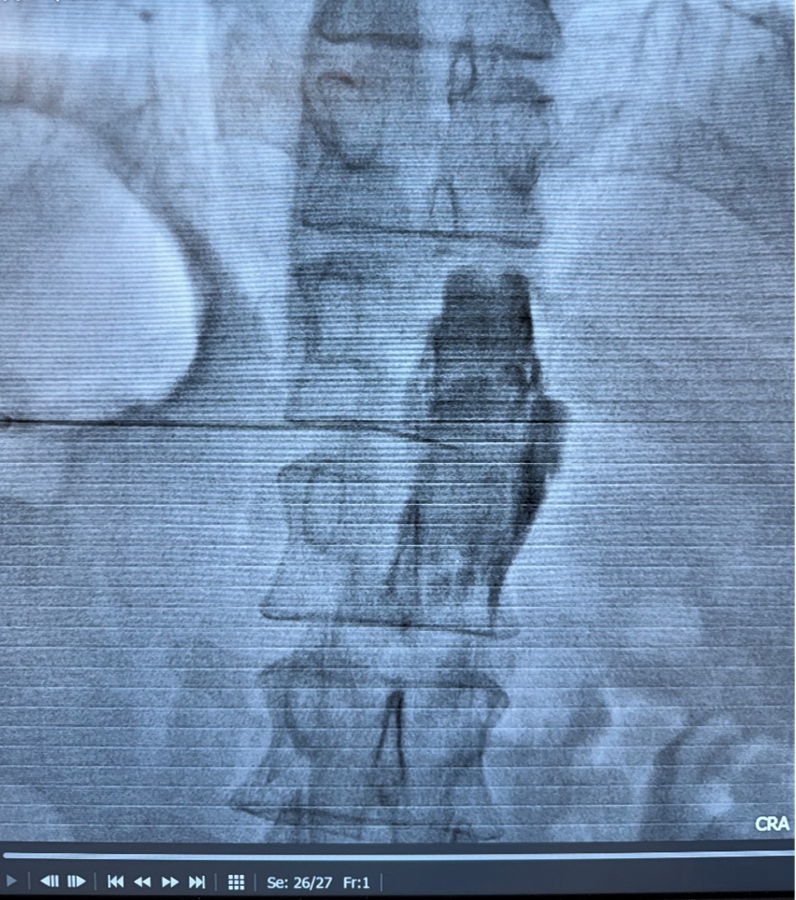

腹腔神经丛毁损术,堪称上腹部癌痛的“定点清除术”。医生在CT与超声影像的双重引导下,将一根细针精准送达传递疼痛信号的腹腔神经丛,注入少量神经毁损药物,即可长期阻断痛觉传导通路。

“这项技术的核心就是‘精准’,”医生解释道,“不用像口服药那样走全身血液循环的‘远路’,直接对准疼痛的‘信号指挥部’下手,实现‘釜底抽薪’式镇痛。”